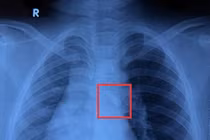

chan-thuong-nieu-dao.jpg

Cơ chế chấn thương niệu đạo khi đi xe đạp - Ảnh minh họa BVCC

PGS.TS.BS Phạm Ngọc Thạch – Phó Giám đốc Bệnh viện Nhi đồng 2 cho biết, tai nạn va đập vùng tầng sinh môn vào vật cứng như sườn xe đạp, thành cầu, nắp cống... trong y khoa gọi là chấn thương dạng "cưỡi ngựa". Khi tai nạn xảy ra, niệu đạo trước bị ép mạnh giữa vật cứng và xương mu dẫn đến giập nát, rách hoặc đứt đoạn.